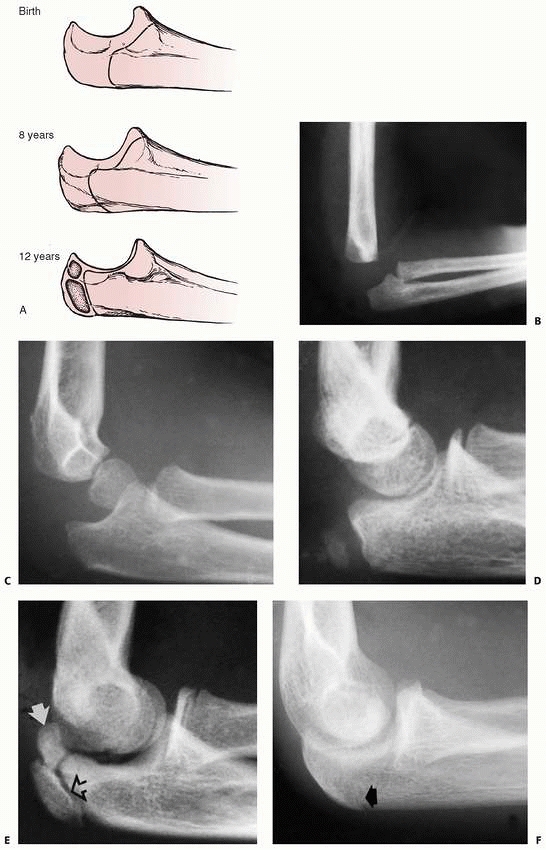

weeks of gestation. By 4 years of age, the radial head and neck have

the same contours as in an adult.71 Ossification of the proximal radius epiphysis begins at approximately 5 years of age as a small, flat nucleus (Fig. 11-1).

This ossific nucleus can originate as a small sphere or it can be

bipartite, which is a normal variation and should not be misinterpreted

as a fracture.11,60,99

FIGURE 11-1 Ossification pattern. A. At 5 years, ossification begins as a small oval nucleus. B. As the head matures, the center widens but remains flat. C.

Double ossification centers in developing proximal radial epiphysis. Reprinted with permission from Silberstein MJ, Brodeur AE, Graviss ER. Some vagaries of the radial head and neck. J Bone Joint Surgery AM 1982; 64. |